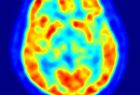

Una parte del cerebro humano funciona como Internet

PALMA DE MALLORCA (EP). El doctor Francisco Barceló, responsable del equipo científico del UNICS, ha liderado la investigación, llevada a cabo de forma conjunta con la Universidad de California (EE.UU.), y que ahora recoge la revista 'Neuron'. Así, el estudio concluye que esa parte del cerebro humano funciona "en red", lo que significa que si a consecuencia de una lesión física esa región sufre daños irreparables los circuitos neuronales se "reconfiguran en cuestión de segundos", estableciendo nuevas conexiones y permitiendo que fluya la información de nuevo.

"Ello no conlleva la reparación del daño, sino que éste se ve compensado gracias a la gran plasticidad de esa parte del cerebro, en la que se encuentra una red flexible y dinámica de interconexiones neuronales", ha explicado el doctor Barceló en declaraciones a Europa Press.

Así, el investigador destaca que la importancia del descubrimiento reside en que durante décadas la parte prefrontal del cerebro fue un "misterio" y se la llegó a considerar "silente". "La comunidad científica llegó a pensar que no tenía ninguna función, debido a que muchos pacientes que habían sufrido lesiones en el córtex prefrontal mostraban una recuperación asombrosa de sus facultades, como si no hubieran sufrido ningún daño", ha relatado.

La explicación, aclara Barceló, se encuentra en la gran "plasticidad neuronal" de esa parte del cerebro, lo que permite superar lesiones gracias a la "continua reconfiguración" de las conexiones neuronales.

La región prefrontal controla la parte más "intrínsecamente humana" del cerebro, relacionada con "la capacidad de comprender el lenguaje hablado, de recordar el pasado o sentir y emocionarnos con esos recuerdos. Afecta a la capacidad de planificar el futuro, o ser animales sociales", detalla el investigador de la UIB.

Esta automática compensación del daño no sucede con la parte occipital (vista) o la parte motora del cerebro, dado que si se produce una lesión en esas regiones el daño es difícilmente reducido.

Así, los investigadores han establecido una comparación entre el cerebro y la red y han concluido que las neuronas se comportan como si navegaran por Internet, quedando probada la gran capacidad para "readaptarse" al nuevo entorno tras una lesión. "La existencia de Internet nos ha ayudado mucho a entender nuestro cerebro", ha concluye el doctor Barceló.